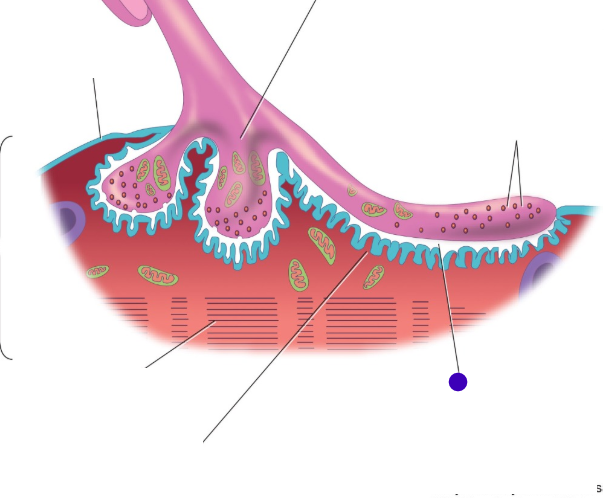

Motor end plate

knowt flashcard image

Synaptic cleft

Neuromuscular junction

<p></p>